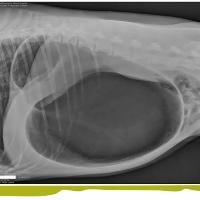

Diagnosis and Management of Splenic Diseases

Ashley Magee, DVM, DACVS, discusses the spleen and emergency management of patients with splenic diseases. Diagnosis and patient stabilization are covered with a majority of the talk focused on surgical technique for splenectomy and the decision…